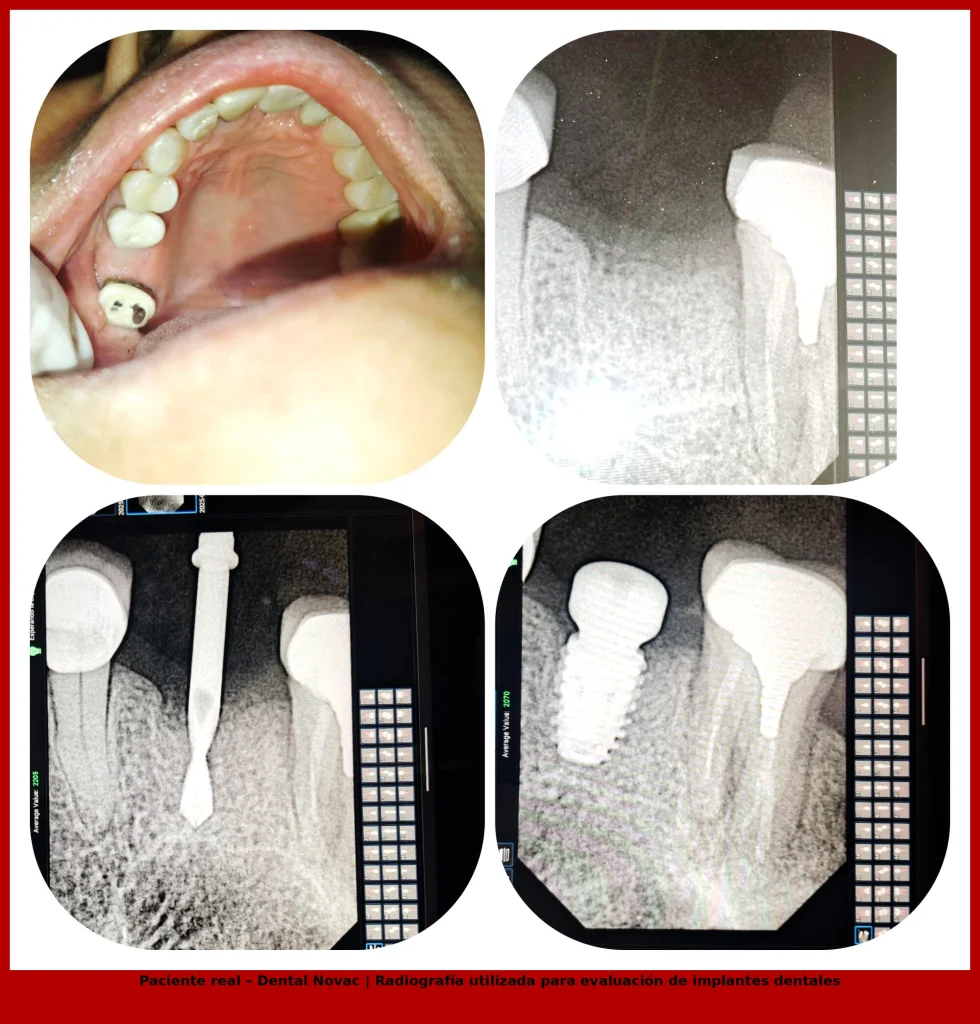

CASO CLÍNICO REAL

La radiografía muestra un implante dental colocado en el hueso maxilar para reemplazar una pieza perdida. Este tipo de tratamiento permite recuperar la función masticatoria y la estabilidad de la dentadura cuando un diente natural ya no puede conservarse.

Según información médica de MedlinePlus (NIH) , los implantes dentales actúan como raíces artificiales que se integran al hueso y permiten colocar coronas o prótesis con resultados duraderos.